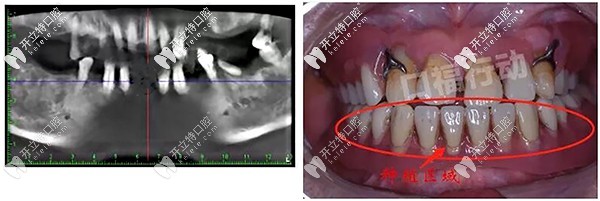

牙齒情況:下半口牙齒僅剩4顆,伴有松動情況,而且有比較嚴峻的牙周炎,牙槽骨也有一點萎縮。

譚醫(yī)生根據(jù)顧客牙齒情況,推薦瑞士iti親水款種植體,這款種植體骨結(jié)合能力強,而且對牙周炎顧客比較友好,臨床使用壽命有40年驗證。

手術(shù)方案:allon4半口即刻負重種植牙,用4顆種植體采用傾斜植入方式,2個小時手術(shù)過后就可以吃東西。